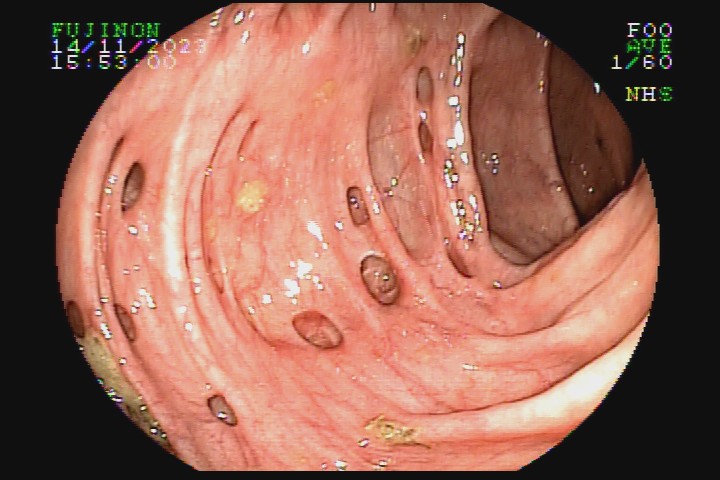

A diverticulose é uma doença adquirida, frequente entre pessoas mais idosas. Acredita-se que tenha como principal fator etiológico hábitos dietéticos relacionados com o refinamento da dieta industrializada. Pode ter uma evolução benigna por toda a vida e ser totalmente assintomática, mas pode também caracterizar-se como doença de sinais e sintomas agressivvos, com considerável morbidade e mortalidade devido às suas principais complicações: inflamação e sangramento.

A diverticulose cólica é consequência da herniação da mucosa do intestino grosso por entre as fibras musculares da parede intestinal. A diverticulose do cólon esquerdo complica mais com inflamação, e a diverticulose do cólon direito complica mais com sangramento.